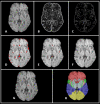

Cerebral microbleeds, observed as small, spherical hypointense regions on gradient echo (GRE) or susceptibility weighted (SWI) magnetic resonance imaging (MRI) sequences, reflect small hemorrhagic infarcts, and are associated with conditions such as vascular dementia, small vessel disease, cerebral amyloid angiopathy, and Alzheimer's disease. The current gold standard for detecting and rating cerebral microbleeds in a research context is visual inspection by trained raters, a process that is both time consuming and subject to poor reliability. We present here a novel method to automate microbleed detection on GRE and SWI images. We demonstrate in a community-based cohort of older adults that the method is highly sensitive (greater than 92% of all microbleeds accurately detected) across both modalities, with reasonable precision (fewer than 20 and 10 false positives per scan on GRE and SWI, respectively). We also demonstrate that the algorithm can be used to identify microbleeds over longitudinal scans with a higher level of sensitivity than visual ratings (50% of longitudinal microbleeds correctly labeled by the algorithm, while manual ratings was 30% or lower). Further, the algorithm identifies the anatomical localization of microbleeds based on brain atlases, and greatly reduces time spent completing visual ratings (43% reduction in visual rating time). Our automatic microbleed detection instrument is ideal for implementation in large-scale studies that include cross-sectional and longitudinal scanning, as well as being capable of performing well across multiple commonly used MRI modalities.